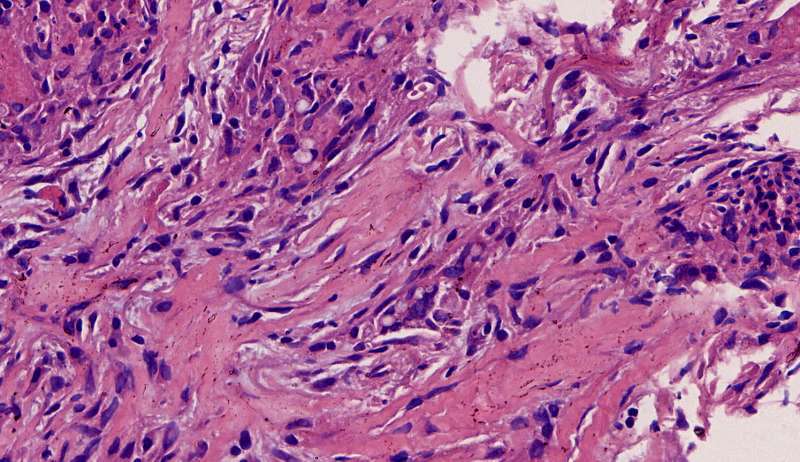

通常有机化

这是个普通慢性炎症结节,有机化(纤维增生团)